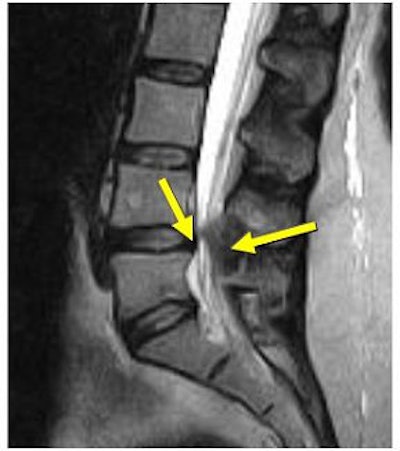

| Increased conspicuity of L4-L5 disk bulge and 2.0 mm increase in stenosis at the L4-L5 level with axial loading. |